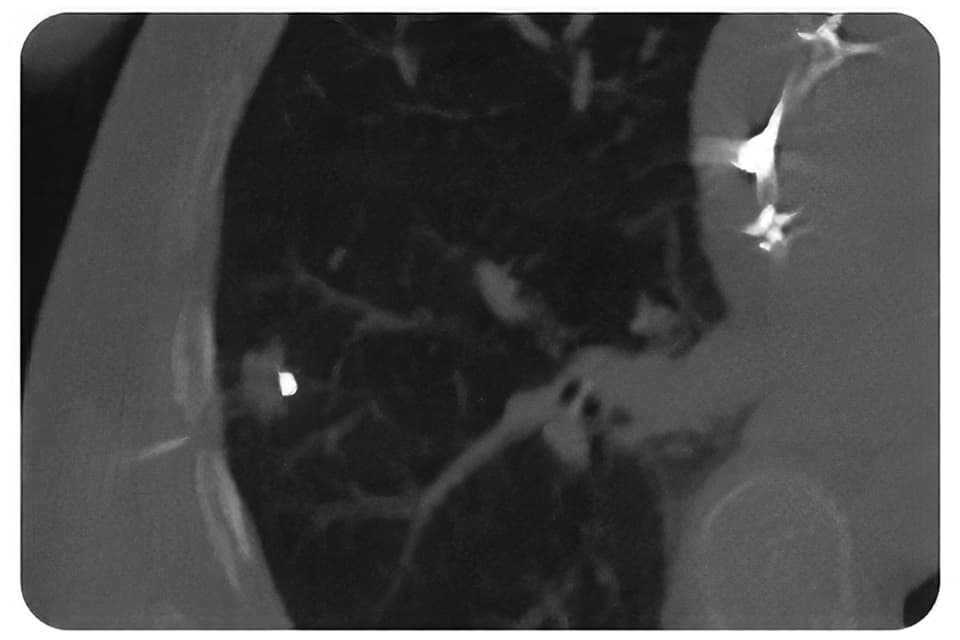

CT

各種画像診断モダリティ(CT、CBCT、kV-X線、MRI、超音波)での明瞭な可視性があります。

Gold Anchorマーカの特徴-3 優れた可視性

Gold AnchorマーカはMRI装置における可視性の向上をはかるため、99.5%の金と0.5%の鉄の合金としています。